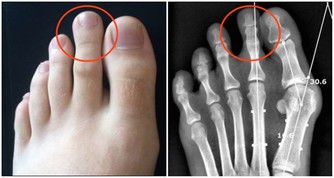

6、發炎

身體為了保全大局,將血液中的病毒和細菌集中在一個地方,因此會出現紅腫熱痛的反應,

我們又消炎吃大量的抗生素,又幫了病毒的忙,身體沒有辦法只能進入第7個階段。